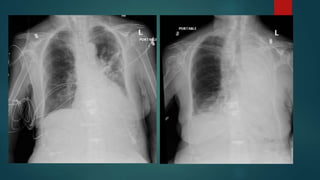

Superior Vena Cava Syndrome

Airway Obstruction

Bleeding